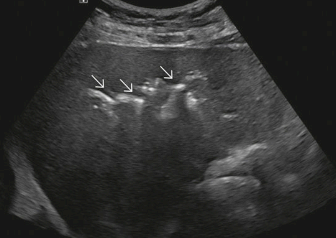

US finding

- 담관과 연결되는 많은 낭포가 있다.

- 담관 내 결석과 반사체가 보인다.